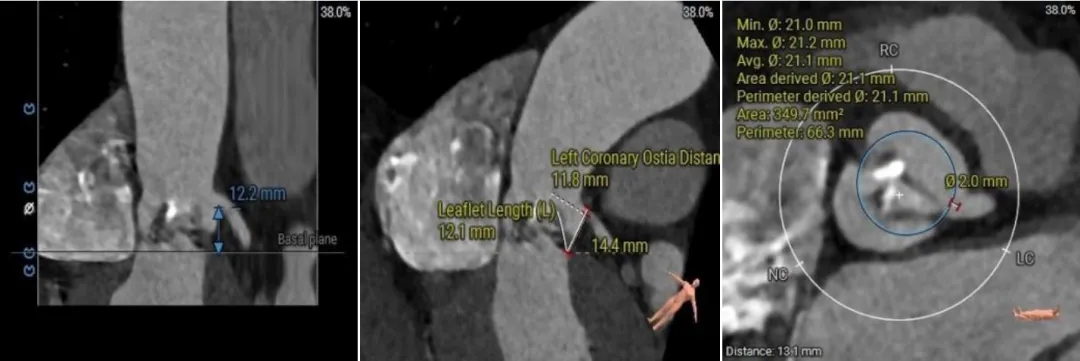

(2)窦部空间较小,左侧瓣叶冗长,且开口位置在短轴平面,左冠冠脉风险较高,优先选择有收腰设计的瓣膜,降低冠脉风险并保留术后足够的VTC

超声医师:患者为重度主动脉瓣狭窄,术前超声充分评估,心腔大小,心腔容量是否充分,各瓣叶活动程度,该病例左侧冠脉风险较高,工作位以及最终释放超声下充分评估原生瓣叶到左冠侧瓣叶距离,进一步评估冠脉风险。